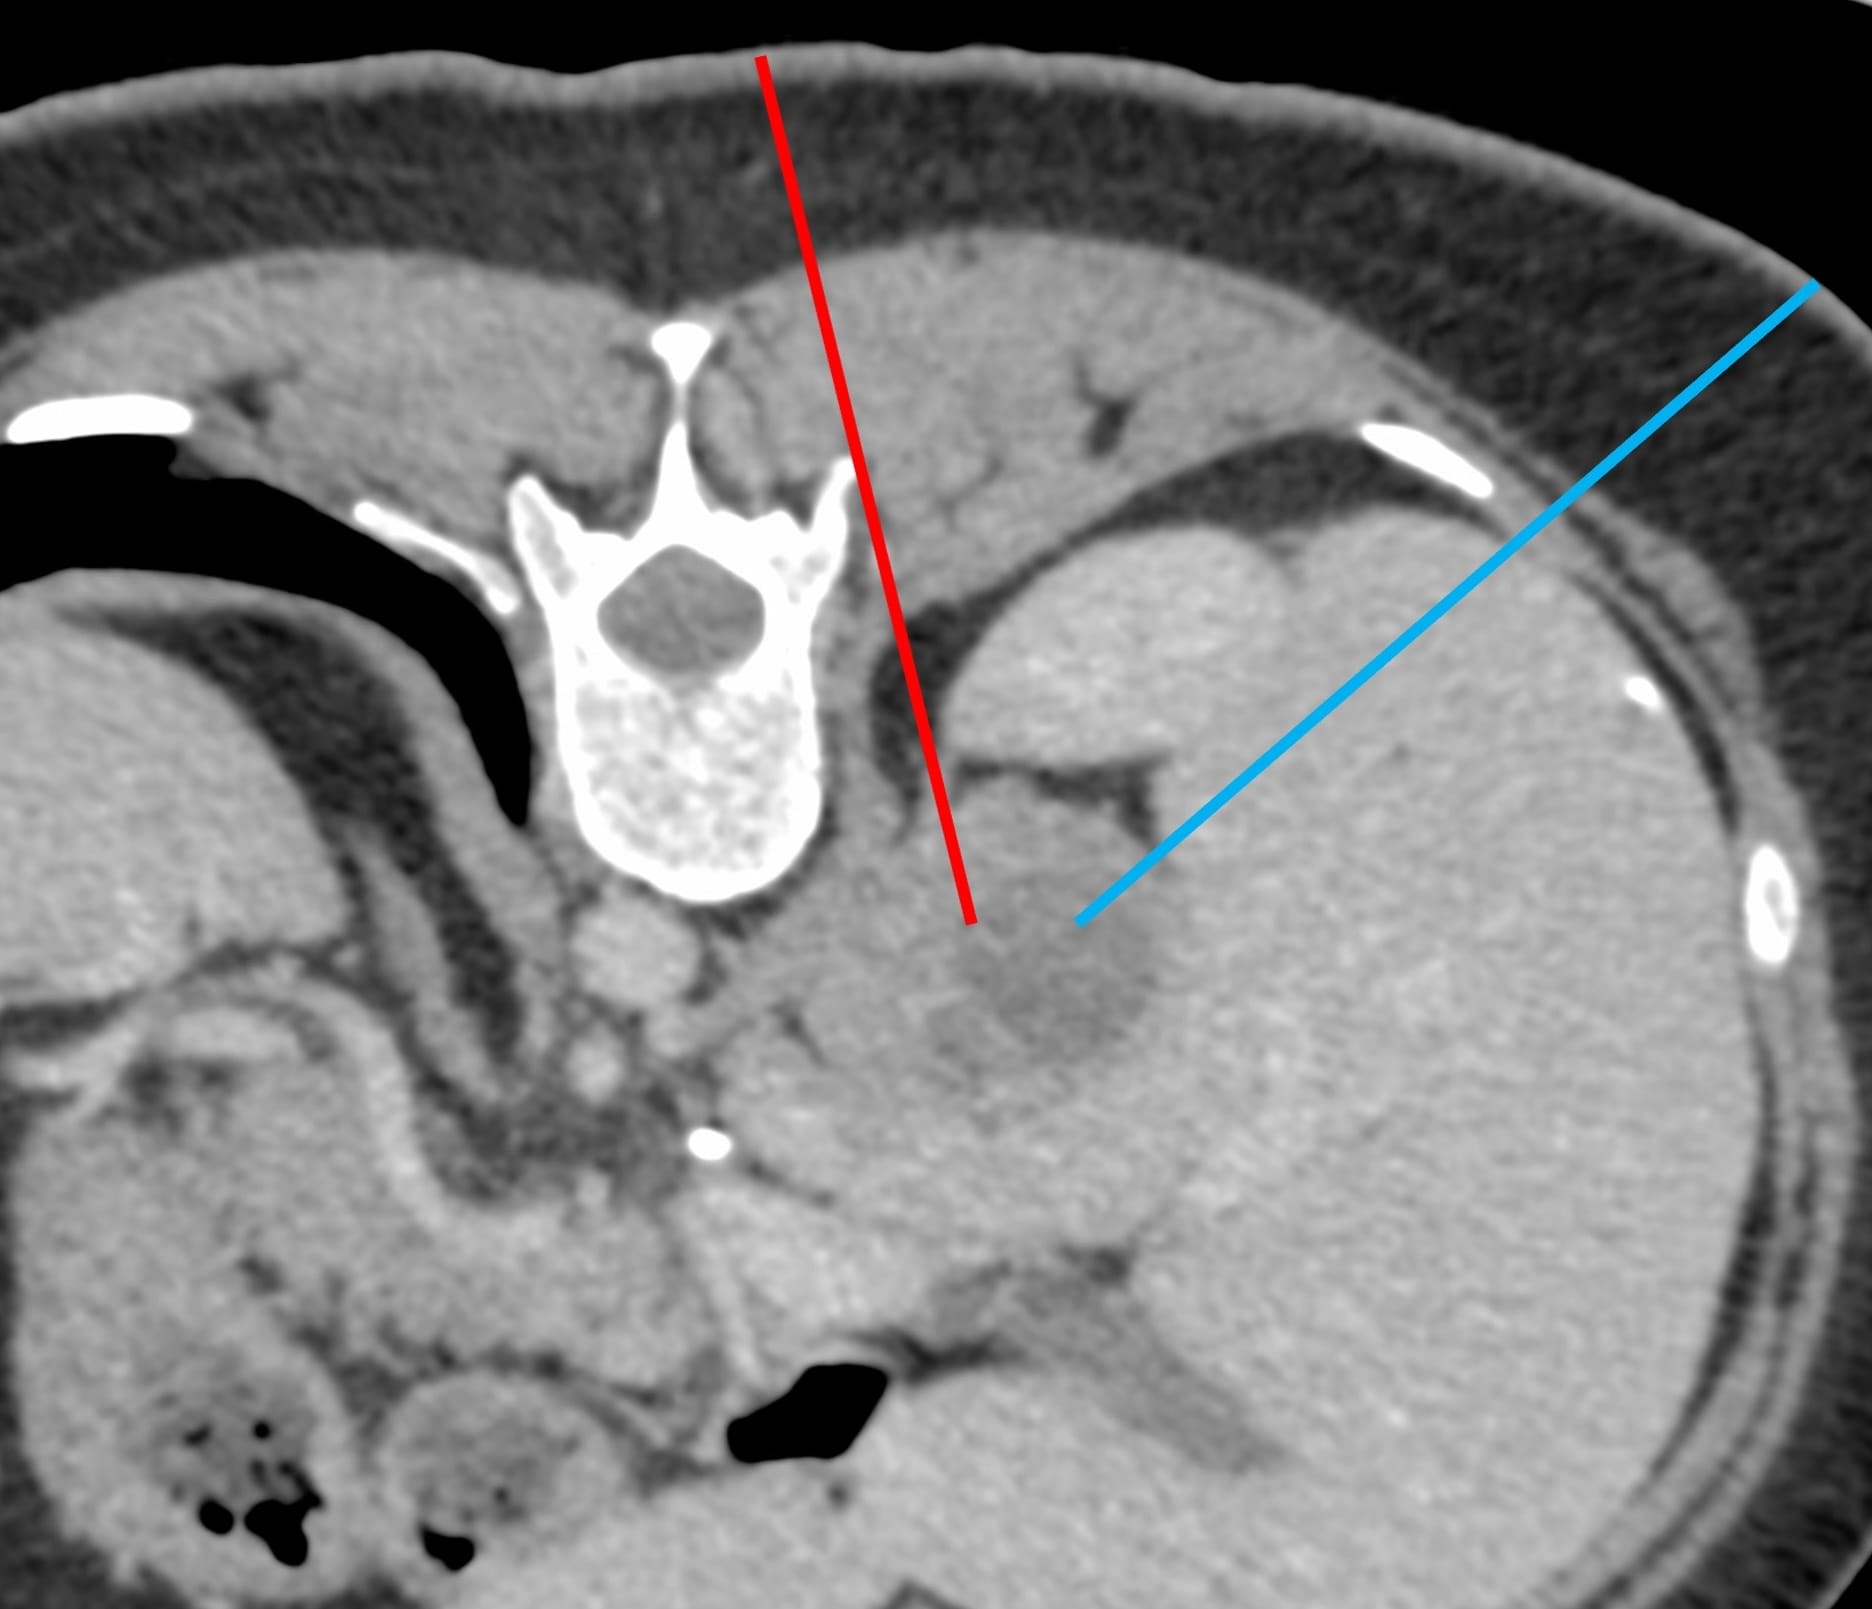

A 40-yrs old presented with a right adrenal gland nodule for biopsy.

What route will you take?

The video discusses the case, the approach to this lesion and a discussion of different adrenal gland biopsy approaches